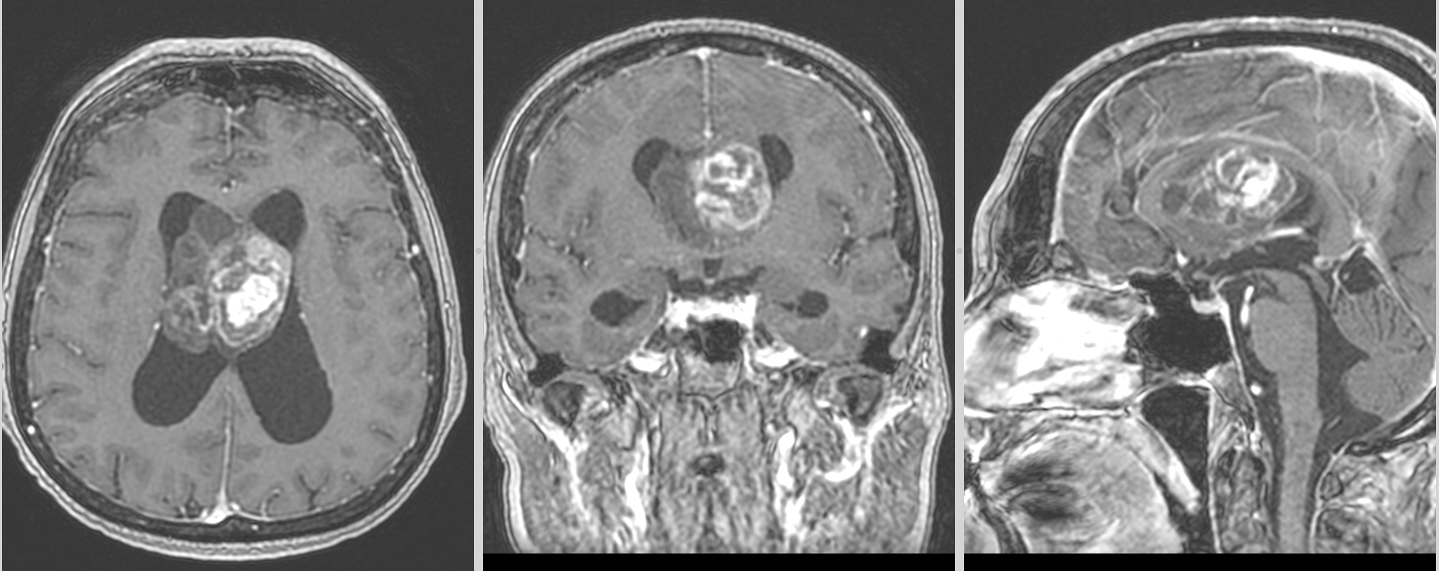

Imagistică – o tumoră „care se arată”

RMN-ul este, de cele mai multe ori, sugestiv:

- localizare intraventriculară, atașată de septul pellucid sau peretele ventricular

- aspect lobulat, uneori polilobat

- zone chistice și calcificări

- captare heterogenă de contrast

Pe CT, calcificările pot fi evidente și ajută la orientarea diagnosticului.